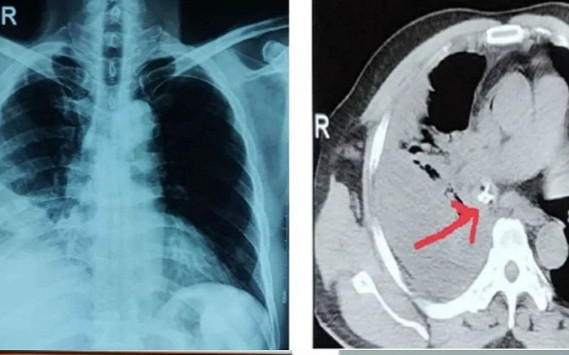

Bệnh nhân được chẩn đoán dị vật phế quản thùy dưới phổi phải biến chứng viêm phổi dưới chít hẹp, kèm theo tràn dịch màng phổi phải.

Bệnh nhân được điều trị kháng sinh tích cực, khi tình trạng nhiễm trùng ổn định, bệnh nhân được nội soi phế quản ống mềm, phát hiện dị vật là mảnh mỏ gà có kích thước lớn, hình dạng 3 cạnh thành sắc trong lòng phế quản thùy dưới phổi phải, một cạnh găm vào thành phế quản.

Niêm mạc phế quản xung quanh dị vật phù nề, sung huyết mạnh, dễ chảy máu và tổ chức hạt bao phủ, gây chít hẹp gần hoàn toàn phế quản thùy dưới phổi phải.